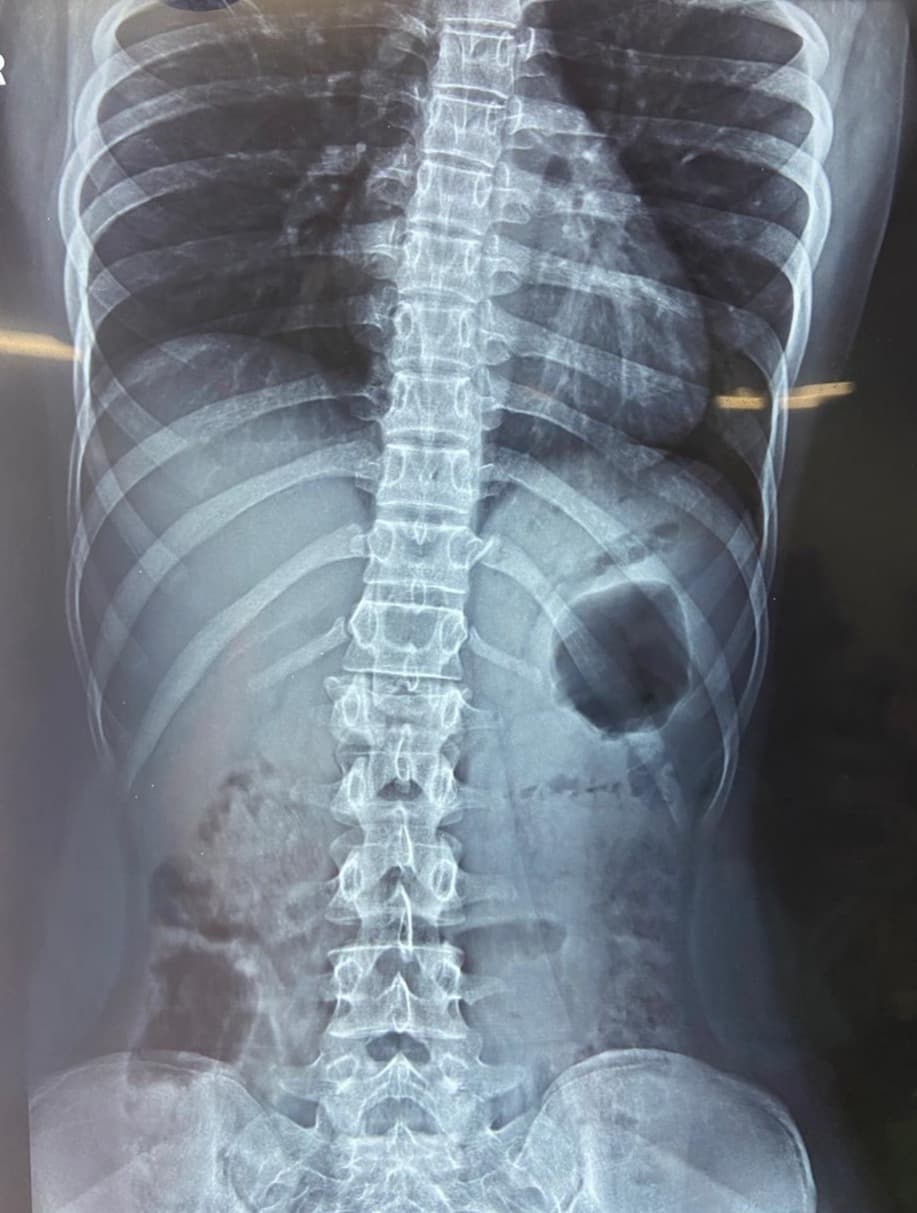

Spine fractures

A 17-year-old girl was brought to us after a fall from the first floor of her house. She had sustained a severe injury to her spine and was unable to walk at the time of admission. X-rays and MRI revealed an L1 burst fracture with compression over the spinal cord. On clinical examination, she had paraparesis—weakness of both lower limbs—with significant difficulty in standing and moving. The family was deeply worried as her ability to walk again was uncertain. Given the severity of the spinal cord compression and the risk of permanent neurological loss, she was taken up for emergency posterior stabilization and decompression of the spinal cord